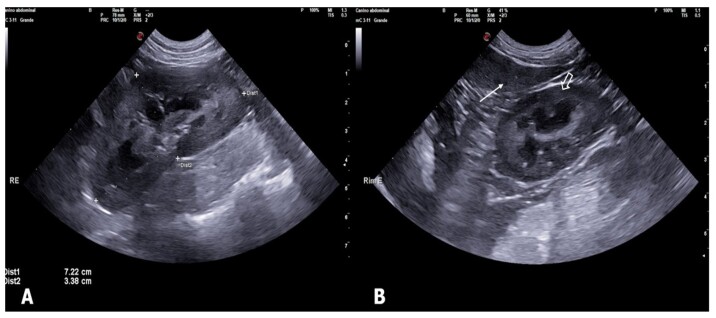

This study evaluated the effects of exposure to tobacco smoke on the kidneys of household dogs using B-mode ultrasonography and Shear-wave Elastography (SWE). Fifteen adult dogs were analyzed and divided into two groups: one exposed to passive smoking for at least two years (n=7) and another non-exposed group (n=8), both without a history of kidney disease. The animals underwent clinical evaluation and laboratory tests, followed by B-mode ultrasonography and renal elastography. Blood test were normal for all individuals. Ultrasonography demonstrated a significant increase in renal echogenicity (p=0.0070, for both right and left kidneys) and irregular contours (p=0.0256 for the right kidney, and p=0.0070 for the left kidney) in the exposed group. The variables echotexture, corticomedullary ratio, and presence of alterations did not vary between the groups (p>0.05). Tissues were harder in exposed dogs (p=0.0492). These findings indicate that exposure to passive smoking may compromise canine kidney health, with early alterations detectable through ultrasonography and elastography. This study highlights the importance of raising awareness about the risks of smoking in domestic environments and underscores the need for further research to deepen the understanding of passive smoking's impact on the renal morphology of domestic dogs.